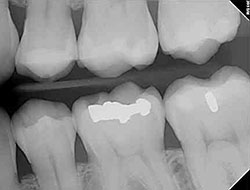

- The digital images can be enlarged and manipulated, giving the doctor a clear, more detailed look at your child's teeth.

- Because your child can see the image enlarged on a screen, she can better understand why taking care of her teeth is important.